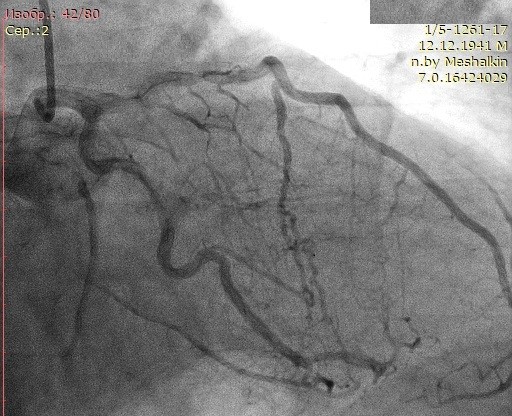

Материал и методы: 90 пациентов с трехсосудистым поражением коронарного русла и обязательным наличием окклюзии правой коронарной артерии (ПКА) в зависимости от варианта развития коллатерального крвоснабжения были разделены на две группы: в первую группу вошли 44 пациента (44%) с наличем коллатералей I и II степени градации по Rentrop, во вторую группу – 46 пациентов (56%) с наличием коллатералей 3 градации по Rentrop. Проанализированы данные перфузионной сцинтиграфии, эхокардиографии и тканевой допплерографии.

Результаты: Выявлено ухудшение перфузии миокарда по нижней стенке у пациента из второй группы при незначимом дефекте перфузии у пациента из первой группы. СДП в 1 группе составил 9,8±3,5%, во второй группе – 4,1±1,7%. При сравнении показателей тканевой допплерографии более значимое изменение продольной деформации в области нижней стенки левого желудочка выявлено в группе с плохим коллатеральным руслом: – 4,1±2,6, во 2 группе: – 6,8±2,7. При оценке сегментарной сократимости нижней стенки левого желудочка выявлено меньшее количество сегментов гипокинеза в группе 2.

Заключение: Хроническая окклюзия коронарной артерии со слабым коллатеральным кровоснабжением сопровождается худшими показателями локальных перфузии и функции миокарда. При хорошем развитии коллатералей, несмотря на незначимые нарушения перфузии миокарда в покое, имеются отчетливые стресс-дефекты перфузии и нарушения локальной сократимости миокарда.